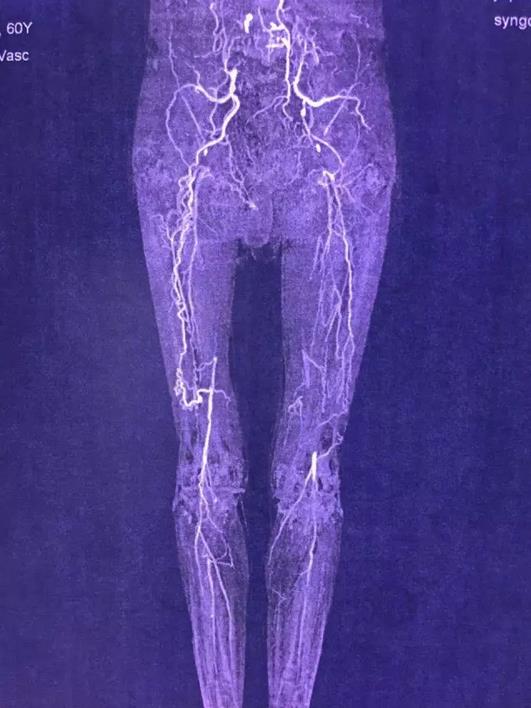

就在入院20多天前,老汉没原由突然觉得左腿疼痛,伴麻木,发凉,无力。赶紧去当地市级医院就诊,查彩超及CTA发现(图1),双侧髂动脉及双下肢动脉长段闭塞!病因是找到了,但当地医院束手无策,巧合的是老汉有一个亲戚是郑州大学五附院的护士长,听说老汉得了这个病,让他赶紧来找王兵教授。护士长告诉老汉王兵教授是河南省血管外科的首席专家,也是郑州大学五附院的副院长、郑州大学血管外科研究所所长,在治疗复杂下肢动脉硬化闭塞性病变上经验非常丰富。

图1 外院CTA

王兵教授亲自接诊了姚老汉,详细询问患者病情,认真细致的进行专科查体。因为外院对诊疗该病经验不足,完成的CTA检查并没有完全包括病变的血管,指示主管医生王颖主治医师进一步完善腹主动脉的CTA检查。很快结果出来了(图2),病变的范围远比想象的大,已经累及了肾动脉以下的整个腹主动脉,病变相当复杂。而患者年龄又比较大,还患有心脑血管疾病,传统的开腹人工血管转流手术,对患者来说创伤太大,心脑血管意外风险极高。

图2 腹主动脉闭塞